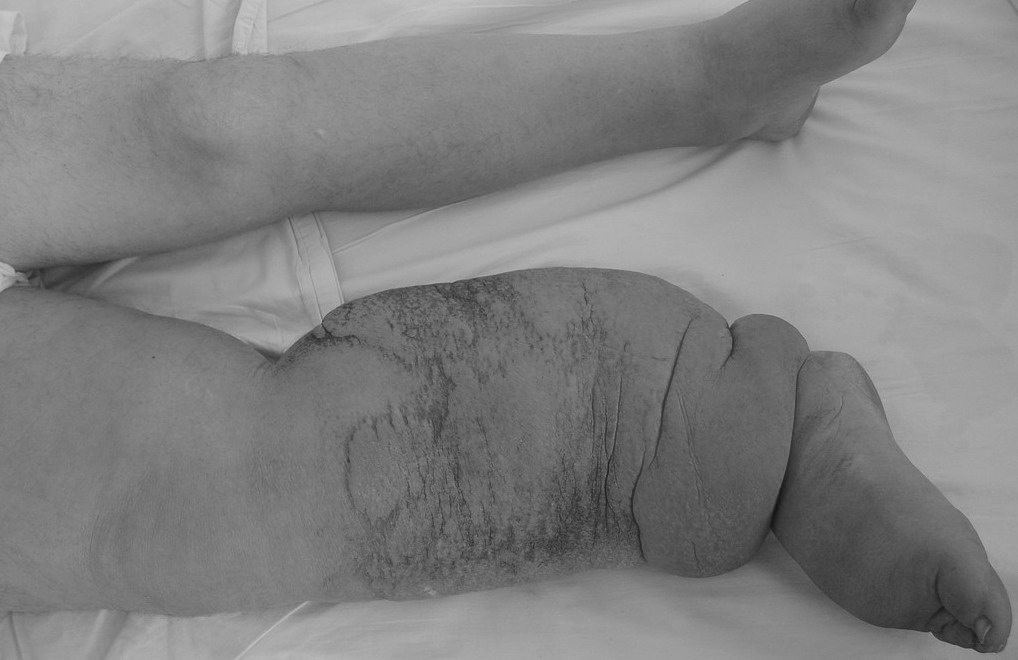

“几十年前,我还偶尔能看到这样一群病人,他们面黄肌瘦,明显看就是营养不良。但是,在那个时代,生活水平都普遍不好,消瘦的病人并不少见。但是,当我看到他们那好似大象的双腿,在地上艰难地拖动着,我知道我这辈子都不可能轻易忘记那一场景..."

因为丝虫感染淋巴系统等组织后,可以在里面“吃喝”“繁殖”,最终刺激局部皮肤增生,同时堵塞淋巴管,导致肿胀。

所以,远远的看,这些被感染的皮肤,就好似大象皮一样厚实。

班氏吴策线虫和马来布鲁线虫引起的丝虫病,也被称为象皮病或象皮肿。

这是因为此2种丝虫,可寄生在人的腿部、阴囊、臂部等皮肤的皮下组织、淋巴系统、腹腔或胸腔内,然后分泌因子刺激皮肤增厚,并堵塞淋巴管,导致淋巴肿大,最终形成厚如大象皮一样的组织。

恶毒的线虫成虫,呈线状,白色,盘曲在人的淋巴结和淋巴管内,“吃喝”可达10-18年之久。